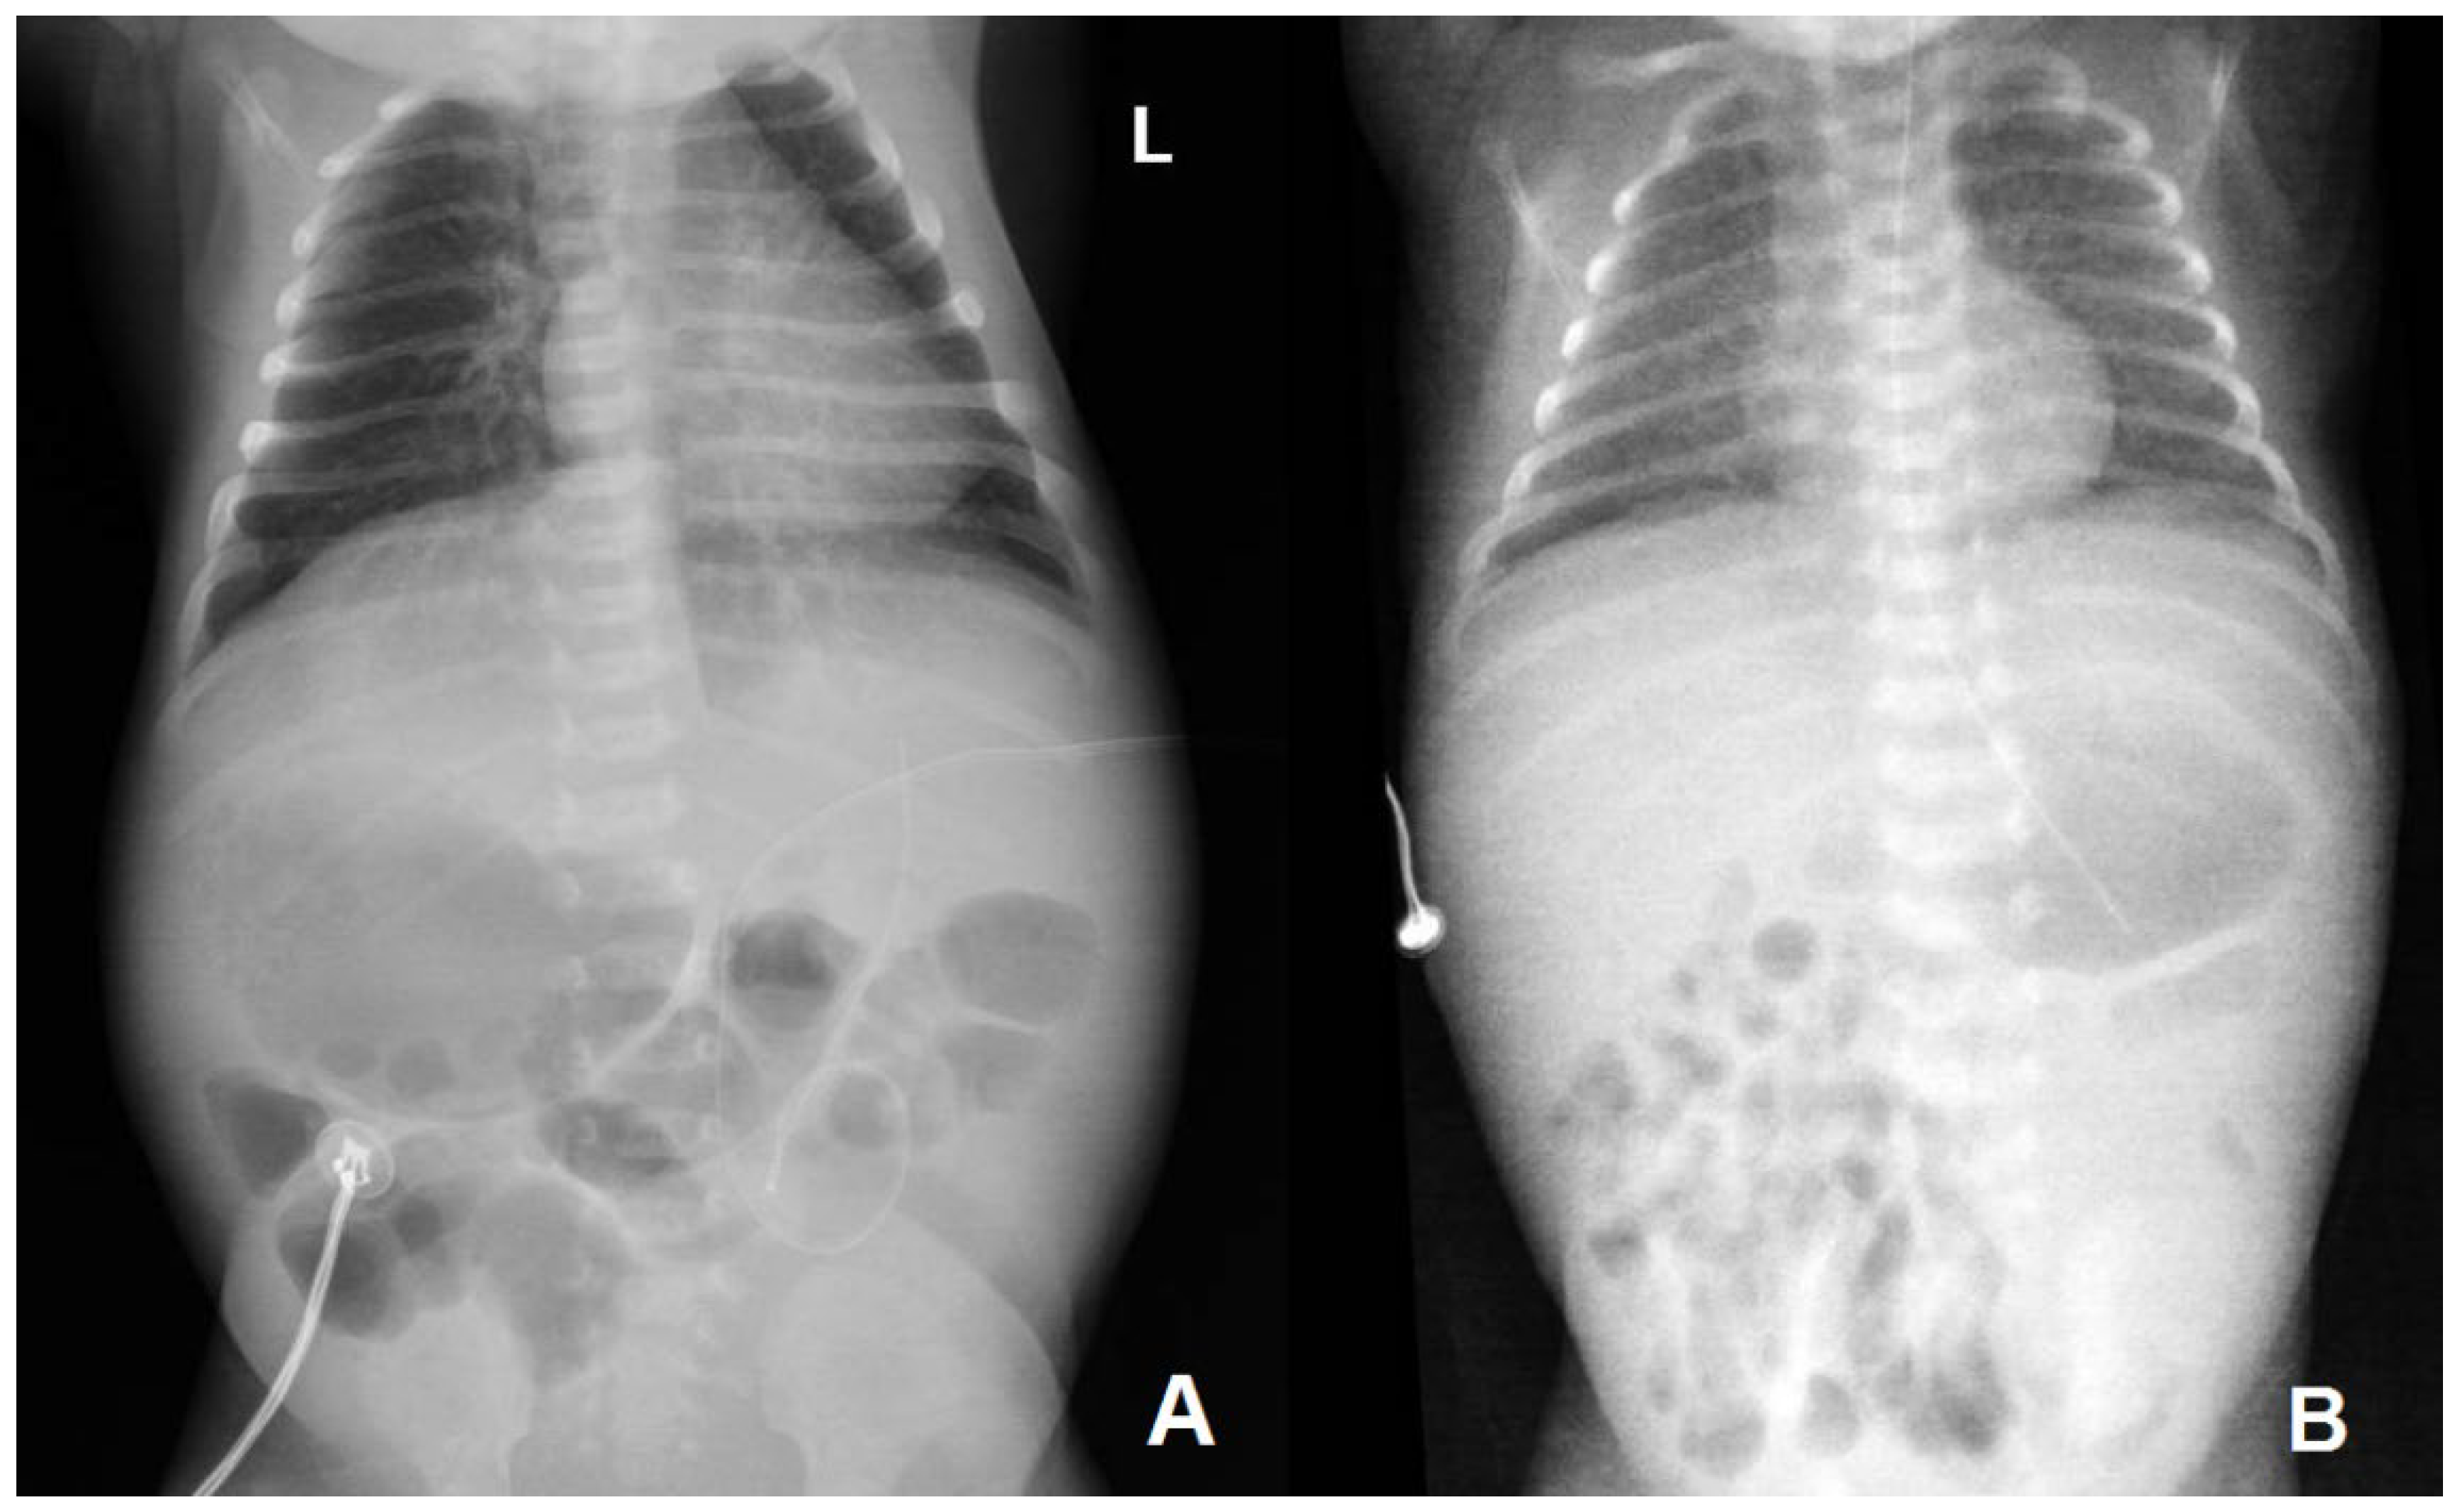

| Thoraco-abdominal radiography | No lung or abdominal involvement | Suggestive of respiratory distress syndrome due to surfactant deficiency on DOL6 0; pronounced reticular, micronodular bilateral lung interstitium on DOL6 5 | |||||||||||

| Abdominal ultrasound | Suspected neuroblastoma on DOL6 1; abdominal situs inversus on DOL6 2; no abdominal parenchymal involvement on DOL6 2 and 10 | Gross, inhomogenous, patchy echogenic areas disseminated, almost throughout the entire liver on DOL6 9; fine granular echogenic areas limited to the fourth hepatic segment by DOL6 14; normal hepatic ultrasound structure on DOL6 45 | |||||||||||